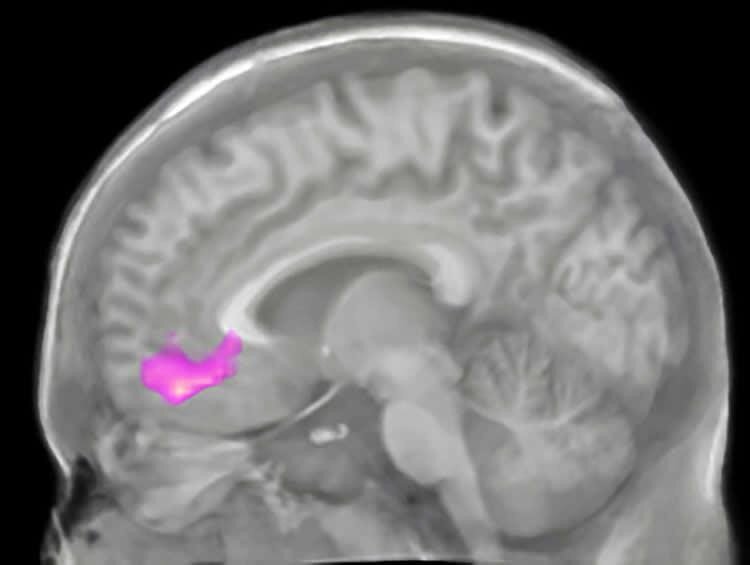

Медиальная префронтальная кора лобной доли. Credit: public domain

В некоторых исследованиях уже показывали, что у более альтруистичных и эмпатичных людей, которые способны задумываться, как их действия могут повлиять на окружение, выявляется высокая активность дорсомедиальной префронтальной коры, участок коры на стыке теменной и височной долей и предклинье. За моделирование будущего же, как выяснилось, отвечают вентромедиальная префронтальная кора, медиальная височная кора и задние медиальные области. Авторы нынешней работы решили выяснить, как система личных ценностей может влиять на восприятие событий в ближайшем и отделанном будущем и как, зная зоны специфические активации мозга, можно эту систему немного изменить, чтобы сделать людей более осознанными.

Далее нейропсихологи сосредоточились на активности в вентромедиальной префронтальной коре и выяснили, что у более альтруистичных участников она активировалась сильнее, когда они сталкивались с далеким будущим по сравнению с ближайшим. Напротив, у эгоистичных добровольцев во всех случаях эта область активировалась одинаково.